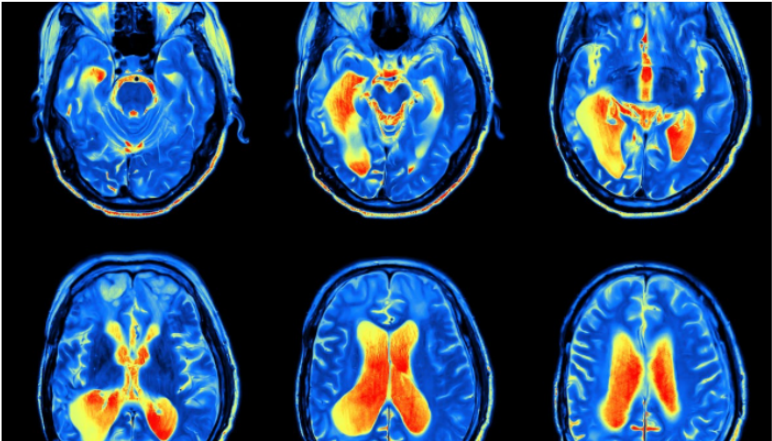

脑部扫描是脑部研究和医学中必不可少的工具,可帮助理解和识别脑部各个区域的问题或障碍。脑部扫描类型可以包括计算机断层扫描(CT)扫描,磁共振成像(MRI)扫描,正电子发射断层扫描(PET)扫描,磁脑图(MEG)扫描等等。MRI扫描技术在提供诸如大脑和组织图像之类的数据方面不同于X射线。

某些类型的脑部扫描可分为结构性脑部扫描或功能性脑部扫描。结构性脑部扫描(例如MRI扫描)处理大脑的结构。这些扫描可以显示不同组织之间的对比,例如脑脊液,灰质,白质等等。研究人员使用它们来了解大脑的解剖结构。功能性脑部扫描用于间接测量脑部功能,例如神经活动。

不同类型的大脑扫描通过各种方法获取大脑活动数据。一些脑部扫描(例如磁共振成像(MRI)或计算机断层扫描(CT)扫描)会无接触地收集数据。信号被馈入X射线或磁场,然后与计算机通信以在大脑扫描中收集数据。脑部的脑电图(EEG)扫描需要头皮接触才能收集数据。脑磁图(MEG)扫描通过距离头皮几毫米的传感器收集数据。受试者必须在扫描仪内保持静止,并且固定的磁传感器阵列位于头部周围。一些脑部扫描需要注射造影剂以收集数据,或者在PET扫描的情况下需要放射活性剂。示例包括大脑的动态CT或MRI扫描。这些技术用于测量脑血容量(CBV)和脑血流量(CBF)